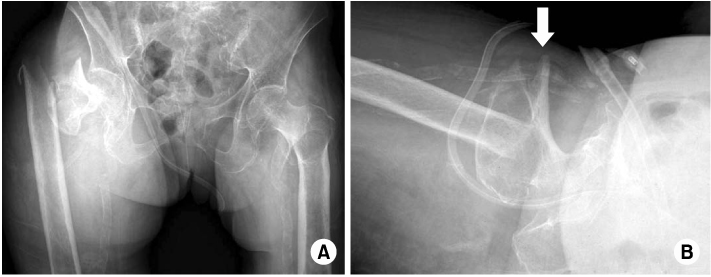

Fig. 3

Computed tomographic angiogram showing the extravasation of contrast material from branch of deep femoral artery.

An 82-year-old woman, previously in bedridden state due to general weakness, was brought to the emergency department by guardians with right hip pain and severe thigh swelling. She was hospitalized at local hospital for 2 years and during stay, only sitting position was possible. Two weeks prior to our hospital visit, she had a history of fall-down from bed but was neglected. The radiographs demonstrated a subtrochanteric hip fracture (Seinsheimer classification grade 2b) with abrupt angulation of the proximal fragment and artherosclerotic vessel (Fig. 1). Additional findings included 30~40 degrees of flexion contracture of knee with severe swelling of the injured limb, more than twice the circumference compared to the contralateral limb (Fig. 2). There were ecchymoses in the anteromedial aspect of the right proximal thigh. The femoral and pedal pulses were symmetric and palpable in both lower limbs. On admission, the blood pressure was 100/80 mmHg with the heart rate of 90 bpm. The initial hemoglobin was 9.5 g/dl with the hematocrit of 0.22. The patient was managed with Buck's traction overnight. She was taken to the operating room the next day and gently placed on the fracture table under spinal anesthesia. The proximal fragment was severely abducted, externally rotated and flexed, making the nail entry into the greater trochanter difficult. Small (3 cm) incision at greater trochanter level was made in order to insert the reduction clamp. Large amount of hematoma was evacuated right after deep fascia incision. Reduction clamp was placed through an incision to reduce the proximal fragment prior to nailing. But, soon after the reduction against the deforming force, active bleeding was observed. The bleeding point was unidentifiable due to massive bleeding and inadequate operative field. Vital sign became unstable with systolic blood pressure dropping to 50 mmHg. Massive gauze packing on the suspected bleeding site was done with rapid intramedullary nail insertion (Proximal Femur Nail, Synthes, Davos, Switzerland). Skin closure and compressive dressing was performed to stabilize the vital sign. Popliteal and pedal pulse was weak. In order to identify the injured vessel, computed tomographic angiography was performed, and active bleeding in one of the branch vessel of right deep femoral artery was suspected (Fig. 3). To further evaluate the injured vessel, emergent digital subtraction angiography was performed. At first, the left common femoral artery was punctured by using a Seldinger technique. Extravasations of contrast medium was identified on the extremity angiogram, originating from one of the minor proximal branch of right deep femoral artery, while filling a 2 cm sized pseudoaneurysm (Fig. 4A). At this stage, coil embolization was attempted to stop the ongoing bleeding. The suspected branch of right deep femoral artery was superselected by using a 2.4 Fr microcatheter (Progreat, Terumo, Tokyo, Japan). Via the microcatheter, attempts were made to completely embolize the injured artery with 13 platinum-made microcoils (Tornado®, Cook Inc., Bloominton, Minnesota, USA), including four 6/2 mm, one 5/2 mm, six 4/2 mm and two 3/2 mm microcoils. Immediately after the embolization procedure, digital subtraction angiography was performed. The angiograms demonstrated complete occlusion of the feeding vessel and the cessation of the active bleeding (Fig. 4B). No other branch except the injured terminal branch was occluded on the angiogram. The day after embolization, the packed gauze was removed surgically.

Fig. 3 Computed tomographic angiogram showing the extravasation of contrast material from branch of deep femoral artery.